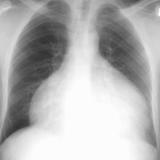

Pericardium

Album: Pericardium

Date: 03/17/2004

Size: 37 items

Views: 76308